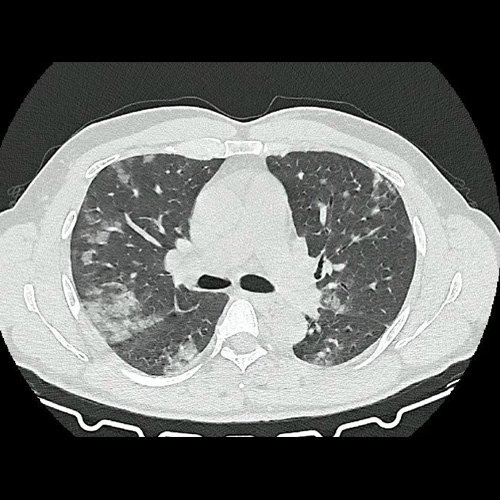

- Tomografía de tórax sin contraste endovenoso (Dia 0):Se observan múltiples áreas de consolidación parenquimatosa con broncograma aéreo y de distribución difusa por ambos pulmones, predominando en los lóbulos inferiores, asociadas a engrosamiento de los septos y rodeadas de tenue vidrio esmerilado. Se identifican estructuras ganglionares lateroaórticas, pretraqueales y subcarinales, ninguna de ellas sin alcanzar rango megálico.

Tomografia de torax sin contraste endovenosos (Ventana pulmonar-corte axial)

Tomografia de torax sin contraste endovenosos (Ventana pulmonar-corte axial)

Tomografia de torax sin contraste endovenosos (Ventana pulmonar-corte axial)